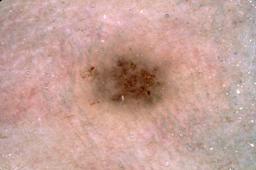

{

"age_approx": 80,

"anatom_site_general": "head/neck",

"concomitant_biopsy": true,

"dermoscopic_type": "contact non-polarized",

"diagnosis_1": "Malignant",

"diagnosis_2": "Malignant melanocytic proliferations (Melanoma)",

"diagnosis_3": "Melanoma Invasive",

"diagnosis_confirm_type": "histopathology",

"image_type": "dermoscopic",

"lesion_id": "IL_0134474",

"melanocytic": true,

"patient_id": "IP_4497472",

"sex": "male"

}